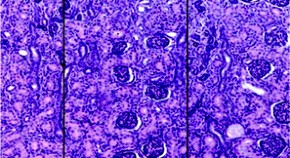

Ciliopathies are caused by alterations in the development and function of cilia. Now Jeffrey Martens and his colleagues demonstrate anatomic and functional rescue of cilia development in mature, differentiated neurons by adenovirus-mediated restoration of expression of the wild-type protein intraflagellar transport protein 88 (Ift88) and show restoration of olfactory function in a mouse model of ciliopathy. A loss-of-function mutation in IFT88 is also identified in individuals with ciliopathies.